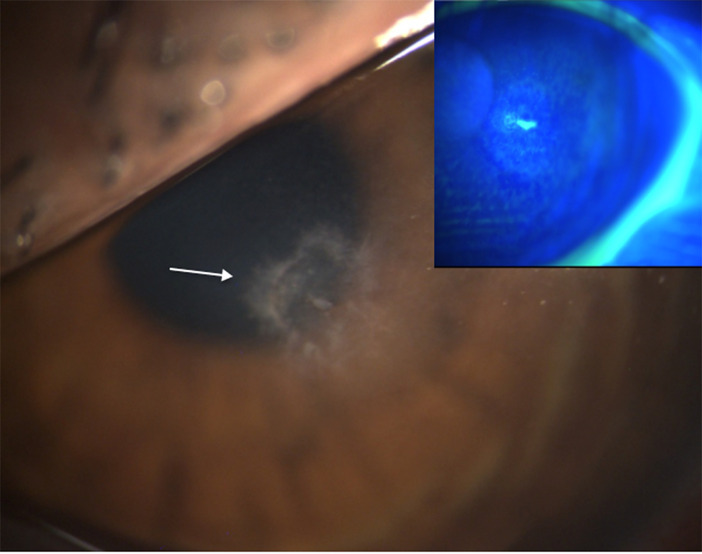

Laser assisted in situ keratomileusis (LASIK) surgery is the leading and most performed refractive surgery nowadays. A possible complication of LASIK surgery is infectious keratitis which can lead to disastrous corneal damage and result in permanent loss of vision. LASIK procedures have become increasingly accessible, and the demand for refractive surgery has risen among patients, challenging the medical field to improve the prevention of post-operative infections. Nevertheless, a wide range of pathogens have been described as responsible for post-LASIK keratitis. However, non-tuberculous mycobacterial keratitis remains an infrequent occurrence and is poorly described in the literature. To the best of our knowledge, this is the first ever reported case of post-LASIK keratitis caused by Mycobacterium wolinskyi. We describe the clinical and microbial characteristics, leading to its challenging treatment choice.